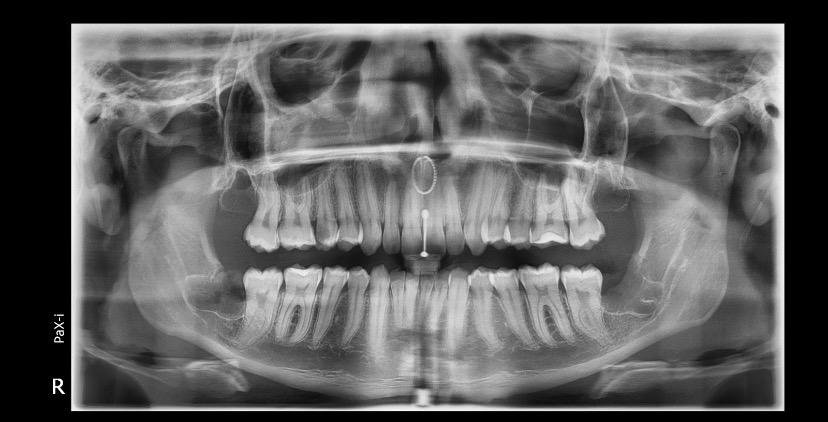

A Patologia Oral e Maxilofacial é a especialidade responsável pelo diagnóstico e tratamento de doenças que afetam a boca, mandíbula e estruturas faciais. Atua na identificação de lesões, cistos e tumores, garantindo diagnóstico preciso e tratamento adequado para preservar a saúde bucal e geral do paciente.